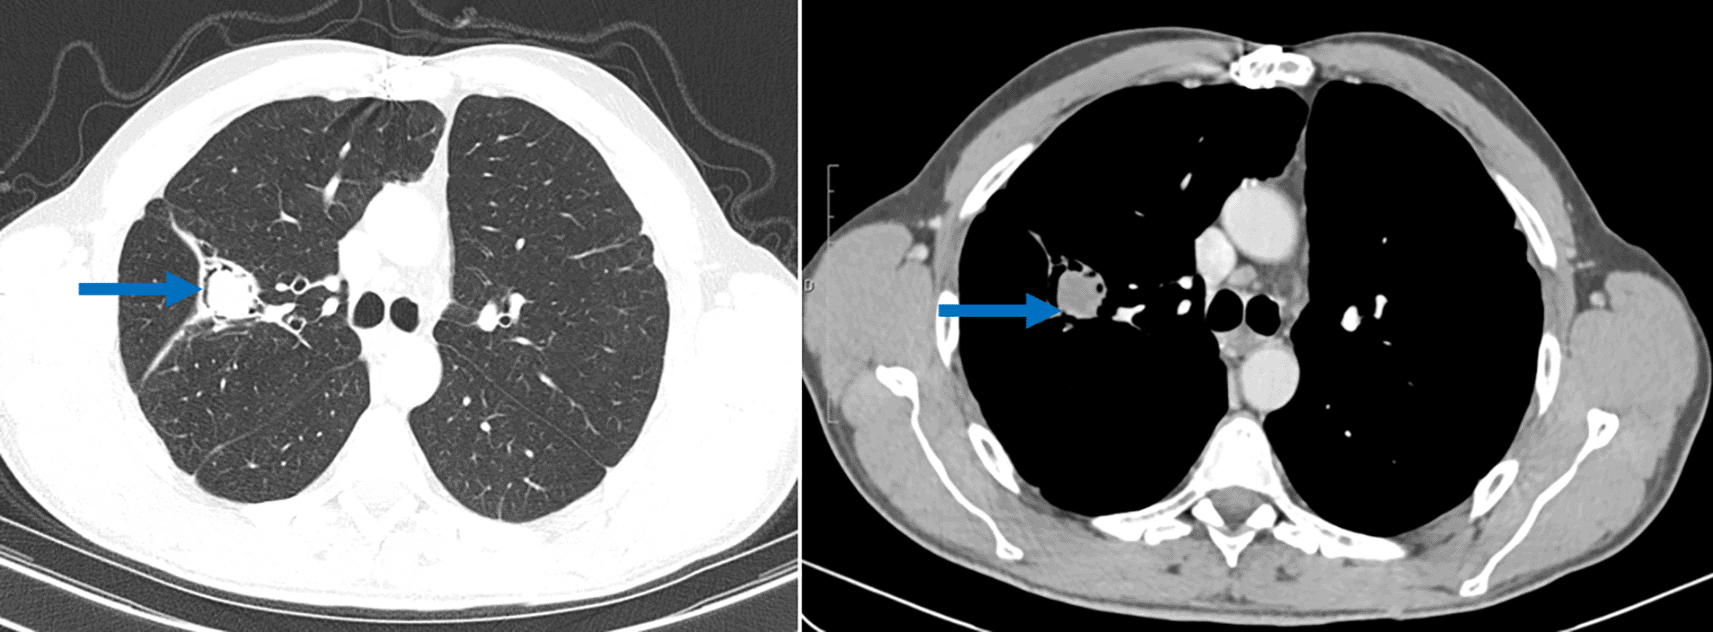

The actual Chest CT scan, performed as part of the etiological assessment of hemoptysis, revealed fluid-density endo-bronchial material in the right superior lobe (lung cavity sequelary to the previous cystectomy) separated from the cavity wall by airspace (“air crescent” sign). This image was typical of pulmonary aspergilloma (Figure 3). Although the Aspergillus serology showed doubtful results, the clinical context together with the CT scan findings were highly suggestive of a pulmonary aspergilloma. Blood tests showed high levels of IgE. A surgical resection of the cavity was scheduled but not yet performed.

Another intriguing finding in this case report was the discovery of an aspergilloma, on the lung cavity. Pulmonary aspergilloma occurs as a colonizer of pre-existing pulmonary cavity of any etiology such as tuberculosis sequelae, cavitary neoplasia or operated hydatid cyst and it is a saprophytic infection.15 Aspergilloma has rarely been described in operated hydatid cyst cavities in immunocompetent patients.16 For this patient, the aspergilloma was discovered twelve years after the lung surgery. A very similar case of a 56-year-old patient, who presented with an aspergilloma of the upper right lobe following cystectomy, have been reported by M. El Hammoumi et al.16 Surgical resection is recommended as a radical treatment for aspergilloma, as was the case with this patient.16